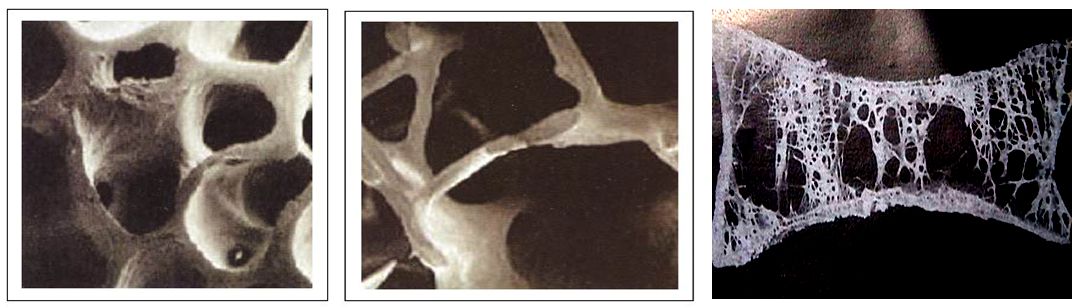

现如今,老年人椎体骨折治疗是医学研究的课题之一,随着老龄化社会的到来,老年人因骨质疏松导致椎体骨折的患者越来越常见。鉴于开放手术的风险太大,而卧床保守治疗,长时间的卧床容易引起呼吸系统、泌尿系感染、心脑血管系统疾病等并发症。患者在治疗一段时间后,常常出现“越治越重”的情况。面对老年人这一特殊群体,“经皮椎体成形术与后凸成形术”——主要针对骨质疏松引起的椎体压缩骨折以及脊椎血管瘤、骨髓瘤、溶骨性转移瘤等肿瘤患者的微创手术,正是解决这一骨科技术难题的最好方法。

治疗目的

(1)增强椎体强度和稳定性。

(2)防止塌陷。

(3)缓解腰背疼痛。

(4)恢复椎体高度。